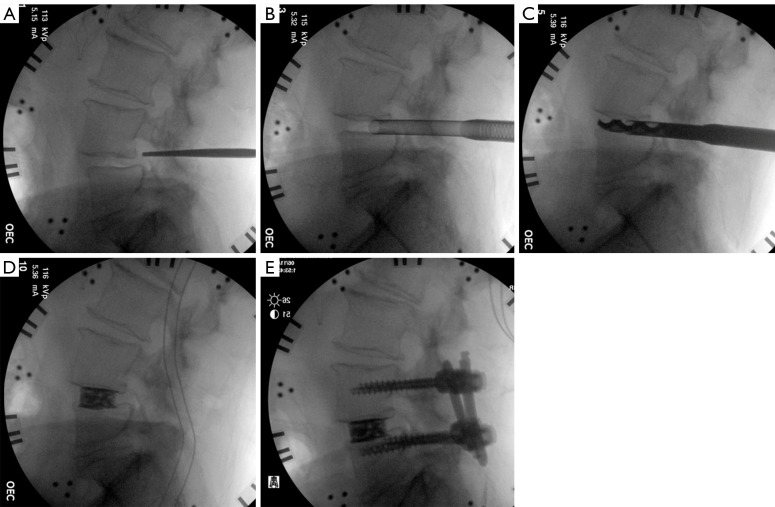

Abstract Image